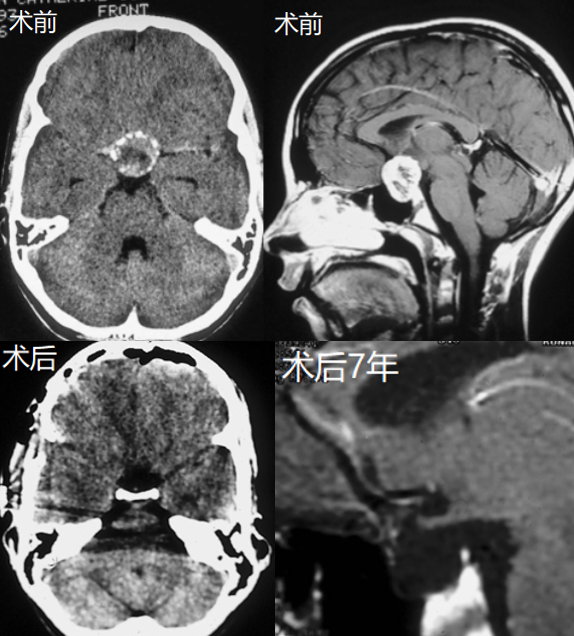

原来这根“救命稻草”也不是谁都能抓住的,但不幸中的万幸是,安达父母的一次勇敢,让他们紧紧抓住了!安达不仅安全全切了这个恼人的肿瘤,更在随访的7年内从未复发。期间,安达还与大部分学生一样,穿上了毕业服,顺利从高中毕业!如今,安达已经回到正常的生活节奏中。阴霾散去,阳光终至。

在手术室外等待良久,安达父母听到了一个好得不能再好的消息:“手术顺利,肿瘤已经被安全全切了!”

“太感谢您了,鲁特卡教授,真的太感谢了……”安达父母双手合十,连声感恩,孩子的未来就这样被一场手术托举。在鲁特卡教授为安达随访的7年时间里,安达不仅没有复发,还在17岁时顺利从高中毕业,她的父母也再一次对教授表达感激。